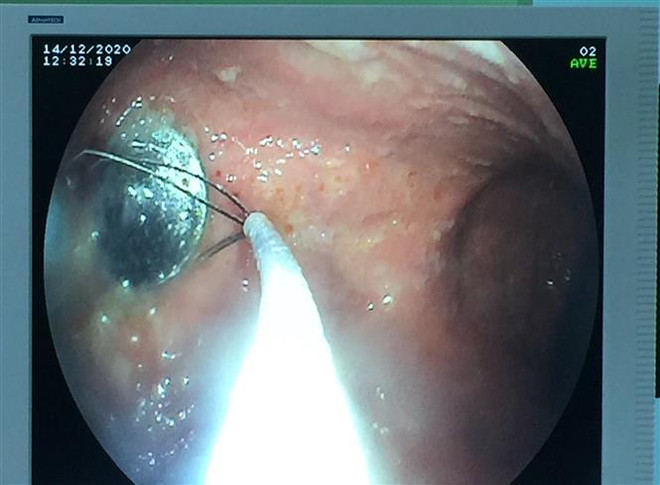

Cấp cứu kịp thời bé gái 4 tuổi nuốt phải đồng xu trong lúc chơi đùa ảnh 1Nội soi gắp đồng xu ra khỏi cơ thể bé gái 4 tuổi. (Ảnh: TTXVN phát)

Chiều 15/12, đại diện Bệnh viện Hoàn Mỹ Đà Nẵng cho biết đơn vị vừa nội soi can thiệp cấp cứu thành công, gắp được dị vật - một đồng xu - nằm ở dạ dày của bệnh nhi 4 tuổi. Hiện sức khỏe bệnh nhi đã hồi phục.

Qua kiểm tra, thăm khám, các bác sỹ xác định có một dị vật hình tròn, nhìn giống đồng xu trong dạ dày của cháu. Các bác sỹ đã hội chẩn và chỉ định nội soi can thiệp thực quản dạ dày để gắp dị vật kịp thời, tránh biến chứng nguy hiểm có thể xảy ra.

Sau 30 phút nội soi can thiệp, các bác sỹ đã gắp một đồng xu kim loại, có đường kính 2cm ra ngoài. Sau thủ thuật, bệnh nhân đã trở lại bình thường, không còn đau, không có biến chứng.